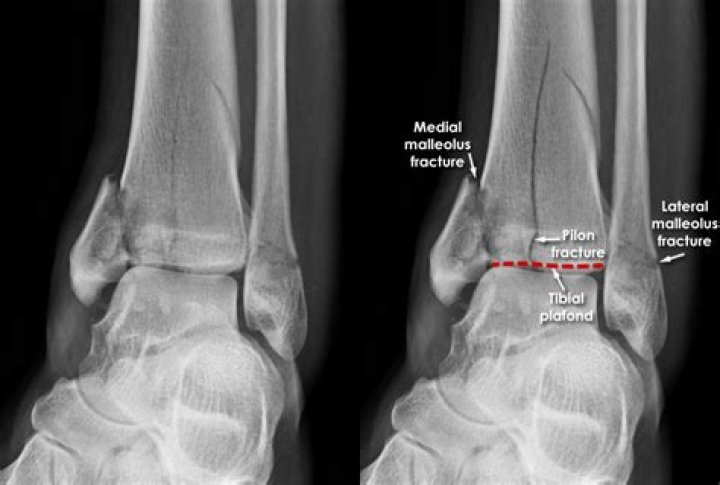

Tibial plafond fractures occur just above the ankle joint and involve that critical cartilage surface of the ankle. The other major factor that must be considered with these injuries is the soft-tissue around the ankle region.

They are also called tibial plafond fractures. One of the common types in children is the distal tibial metaphyseal fracture. This is a fracture in the metaphysis, the part of tibia before it reaches its widest point. These fractures are usually transverse (across) or oblique (slanted) breaks in the bone.